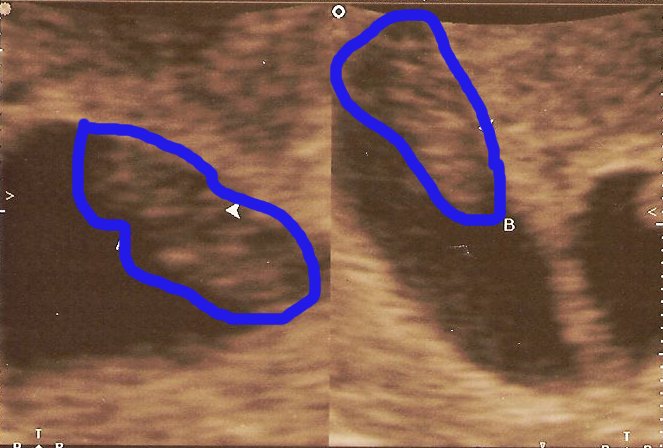

Regina had an appointment with the baby doctor at 8:00 AM yesterday. The nurse operating the ultrasound machine told us she would first look at the top of her stomach before looking at the babies closeup (at 8 weeks, they would be the size of kidney beans). Then she told us something we were not expecting, or prepared for. Regina is carrying TWINS!!!! Both of our jaws had to be picked up off the floor. My eyes were watering, and my head was spinning. The nurse then went in for a closer view to do the measurements, heart rate, etc. These pics are from the closeup view. Even at this small size we could easily see their heart beat. The twins are due November 29, 2007.